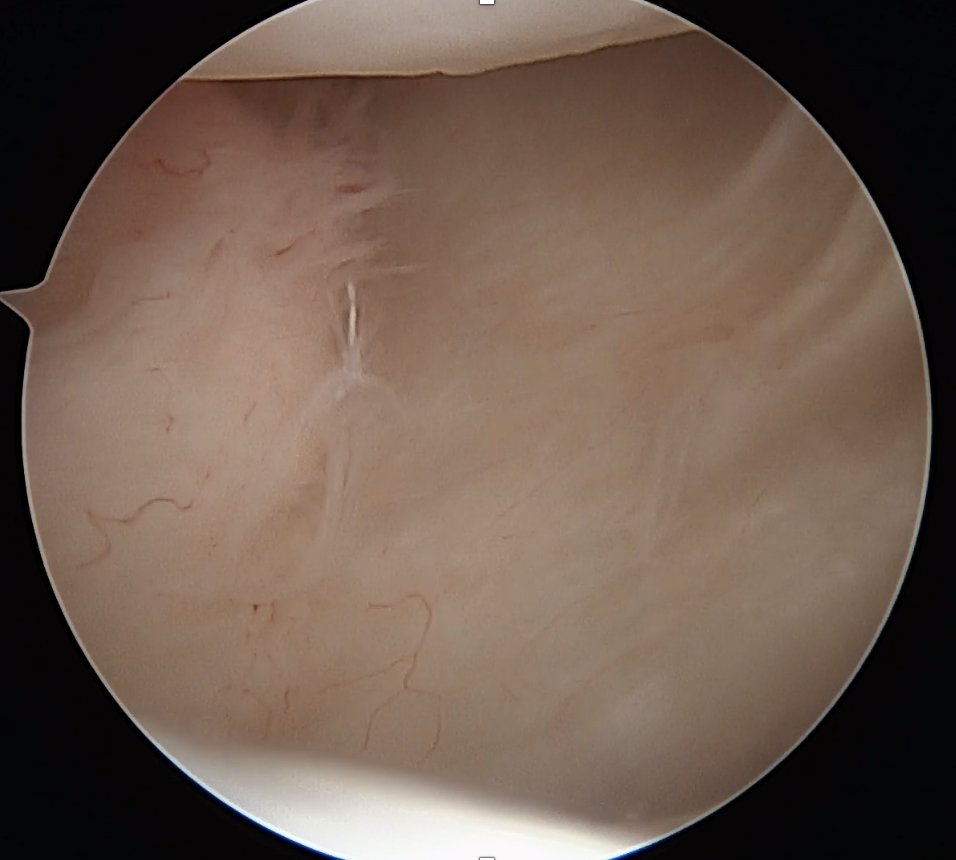

Capsular plication

Indications

Unidirectional anterior shoulder instabiitity

Usually history of trauma on background of ligamentous laxity

No bankart lesion / HAGL / capsular tear

No MDI